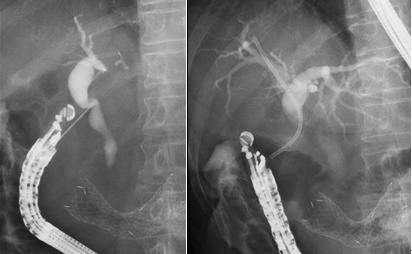

狭まった場所の流れを良くするドレナージ

胆管や膵管の狭くなったところに、プラスチックのチューブや金属性の筒(ステント)を通して流れを良くする方法をドレナージと言います。当院では、一時的に鼻から体外にチューブを出す方法(ENBD)と、短いチューブを留置する方法(ERBD)、金属ステント(Metallic stent)を留置する方法の3つを行っています。

乳頭括約筋切開術

膵管や胆管の出口を切開し結石除去やステント留置を行いやすくします。

バルーン処置

心疾患などがありどうしても抗血小板剤を休薬できない患者様の場合は膵管や胆管の出口をバルーンで拡張し処置を行う場合もあります。

結石除去術・砕石術

小さな結石の場合はバスケットやバルーン状の器具を使用して結石を除去していますが、大きな結石の場合は破砕機を使用して結石を砕いてから除去することもあります。当科では多数結石や大結石に対して、ラージバルーン(太径バルーン)を導入しており、短時間で確実な砕石を可能にしています。

結石破砕の様子